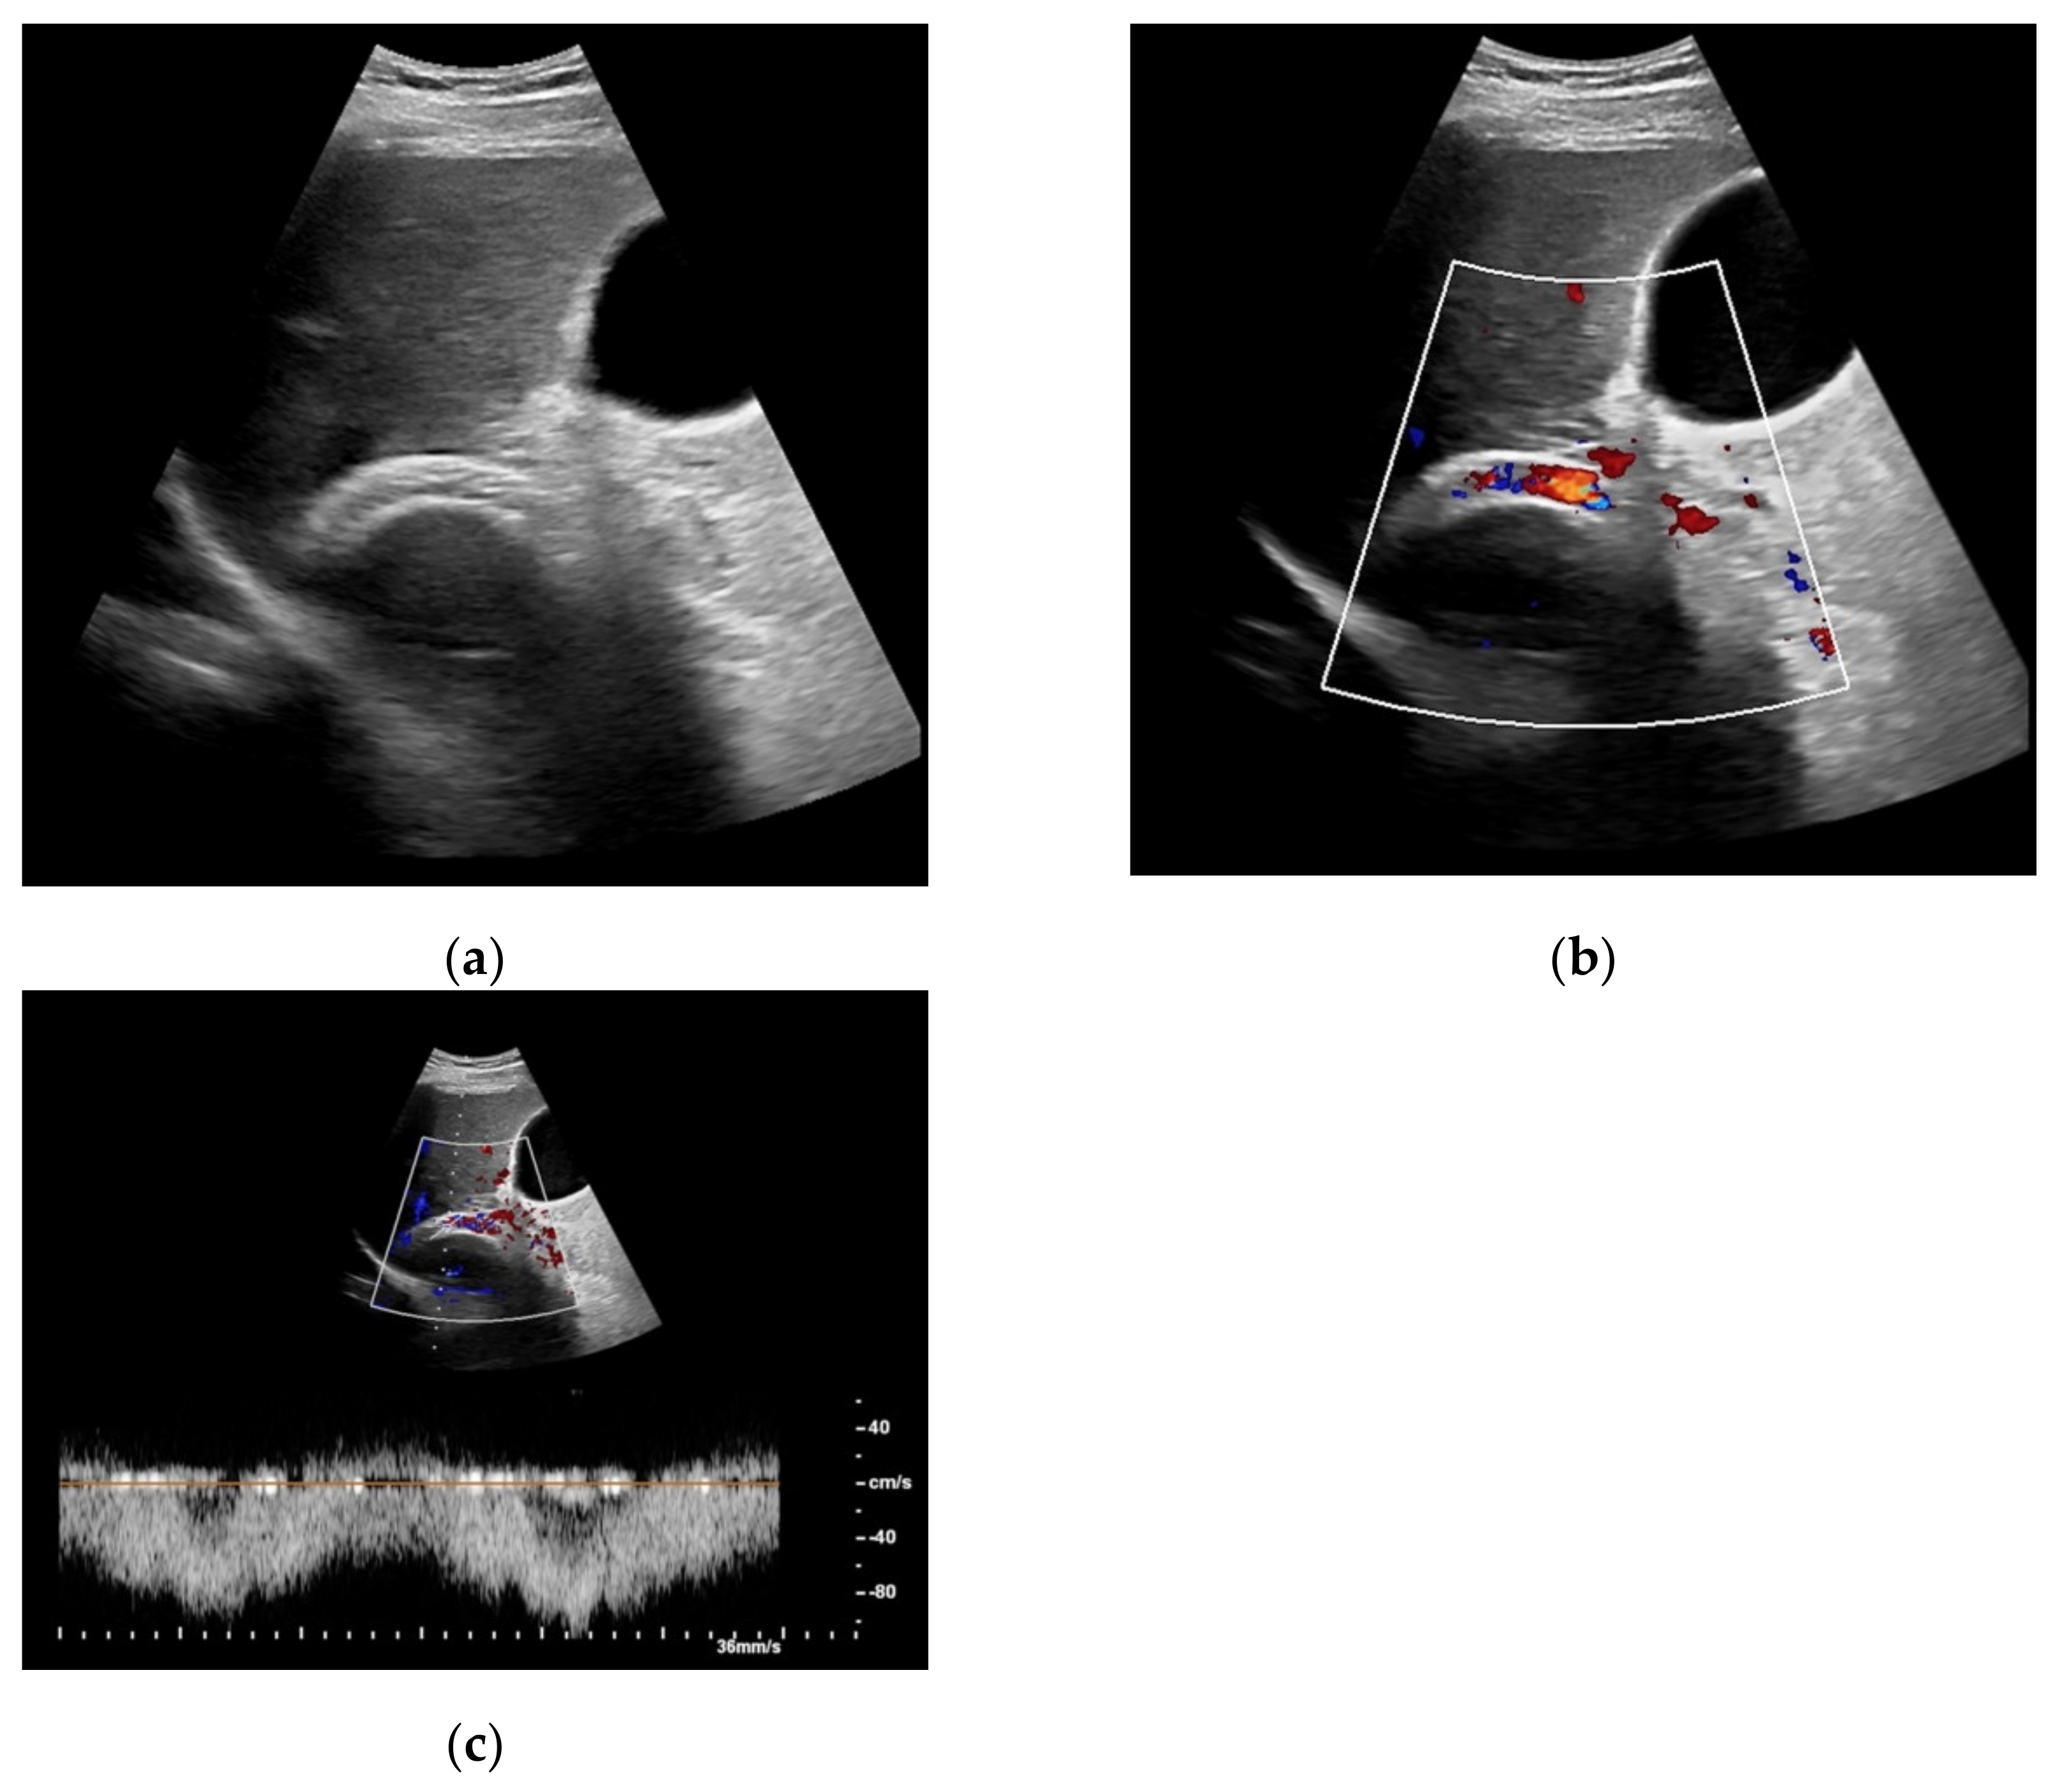

Figure 4. Same patient as in Figure 1 with continuous flow within the transjugular intrahepatic portosystemic shunt (TIPS) without thrombosis or occlusion using microflow imaging (a) and after administration of contrast agent (b,c).